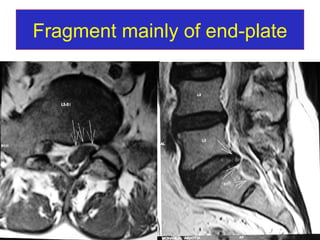

Fragment mainly of end-plate

Follow-up MRI At 3 months At 6 months At 12 months Fragment mainly consist of NP will absorbed in 3 months Fragment mainly consisting of NP+AF will take 6 months – one year Fragment consist of end plate cartilage take longer time – more than 2 years.

Follow-up MRI At3 months At 6 months At 12 months Fragment mainly consist of NP will absorbed in 3 months Fragment mainly consisting of NP+AF will take 6 months – one year Fragment consist of end plate cartilage take longer time – more than 2 years.